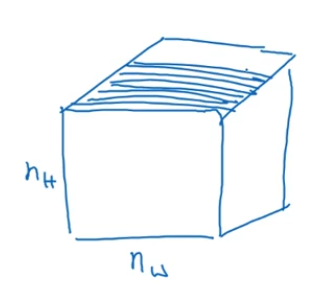

这也是2D向1D的进化,对于3D数据来说如何呢?什么是3D数据?与1D数列或数字矩阵不同,你现在有了一个3D块,一个3D输入数据。以你做CT扫描为例,

这是一种使用X光照射,然后输出身体的3D模型,CT扫描实现的是获取贯穿你的身体的不同片段。

当你进行CT扫描时,就像上图,你可以看到人体躯干的不同切片,本质上这个数据是3维的。一种对这份数据的理解方式是,假设你的数据现在具备一定长度、宽度与高度,

其中每一个切片都与躯干的切片对应。

如果你想要在3D扫描或CT扫描中应用卷积网络进行特征识别,你也可以从3D卷积的第一行开始,为了简单起见,如果你有一个3D对象,比如说是14×14×14